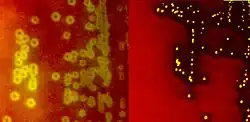

Species of streptococci are classified based on their hemolytic properties.[10] Alpha-hemolytic species cause oxidization of iron in hemoglobin molecules within red blood cells, giving it a greenish color on blood agar. Beta-hemolytic species cause complete rupture of red blood cells. On blood agar, this appears as wide areas clear of blood cells surrounding bacterial colonies. Gamma-hemolytic species cause no hemolysis.[11]

When alpha-hemolysis (α-hemolysis) is present, a blood based agar under the colony will appear dark and greenish due to the conversion of hemoglobin to green biliverdin. Streptococcus pneumoniae and a group of oral streptococci (Streptococcus viridans or viridans streptococci) display alpha-hemolysis. Alpha-hemolysis is also termed incomplete hemolysis or partial hemolysis because the cell membranes of the red blood cells are left intact. This is also sometimes called green hemolysis because of the color change in the agar.

Beta-hemolytic

Beta-hemolysis (β-hemolysis), sometimes called complete hemolysis, is a complete lysis of red cells in the media around and under the colonies: the area appears lightened (yellow) and transparent. Streptolysin, an exotoxin, is the enzyme produced by the bacteria which causes the complete lysis of red blood cells. There are two types of streptolysin: Streptolysin O (SLO) and streptolysin S (SLS). Streptolysin O is an oxygen-sensitive cytotoxin, secreted by most group A Streptococcus (GAS), and interacts with cholesterol in the membrane of eukaryotic cells (mainly red and white blood cells, macrophages, and platelets), and usually results in beta-hemolysis under the surface of blood agar. Streptolysin S is an oxygen-stable cytotoxin also produced by most GAS strains which results in clearing on the surface of blood agar. SLS affects immune cells, including polymorphonuclear leukocytes and lymphocytes, and is thought to prevent the host immune system from clearing infection. Streptococcus pyogenes, or GAS, displays beta hemolysis.